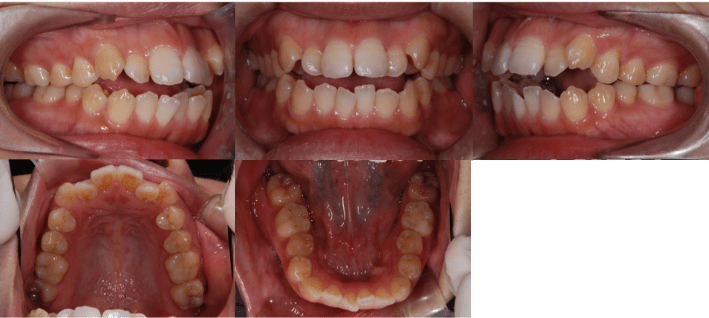

治療前

治療後

• 初診時年齢:28歳4ヶ月

• 主訴:前歯のかみ合わせ

• 診断:開咬

• 治療内容:小臼歯4本を抜歯した後に、マウスピース型カスタムメイド矯正歯科装置(製品名インビザライン 完成物薬機法対象外)を使用して主訴である開咬の改善を行いました。

• 治療期間:2年

• リスク:矯正治療による歯の移動に伴う痛み、歯根吸収、虫歯

• 費用:80万円